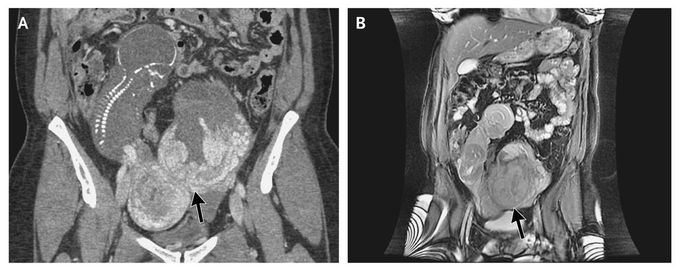

A 30-year-old woman who had a history of two pregnancies and one birth presented with an uncomplicated pregnancy until routine ultrasonography at 19 weeks revealed severe oligohydramnios and a fetus that appeared to be extrauterine. Computed tomography (Panel A) and magnetic resonance imaging (Panel B) of the abdomen and pelvis confirmed an abdominal ectopic pregnancy, with no uterine wall visible surrounding the pregnancy. The fetus was visualized in the right abdomen with a crown-to-rump length of 14 cm, with the placenta attached to the serosa of the uterine fundus (Panel A, arrow). No amniotic fluid surrounded the fetus. The pregnancy was terminated, and surgical removal of the fetus was performed. An abdominal pregnancy refers to a pregnancy that has implanted in the peritoneal cavity, external to the uterine cavity and fallopian tubes. In contrast to tubal ectopic pregnancies, abdominal pregnancies may go undetected until an advanced gestational age. Abdominal pregnancies are associated with a high rate of maternal complications.